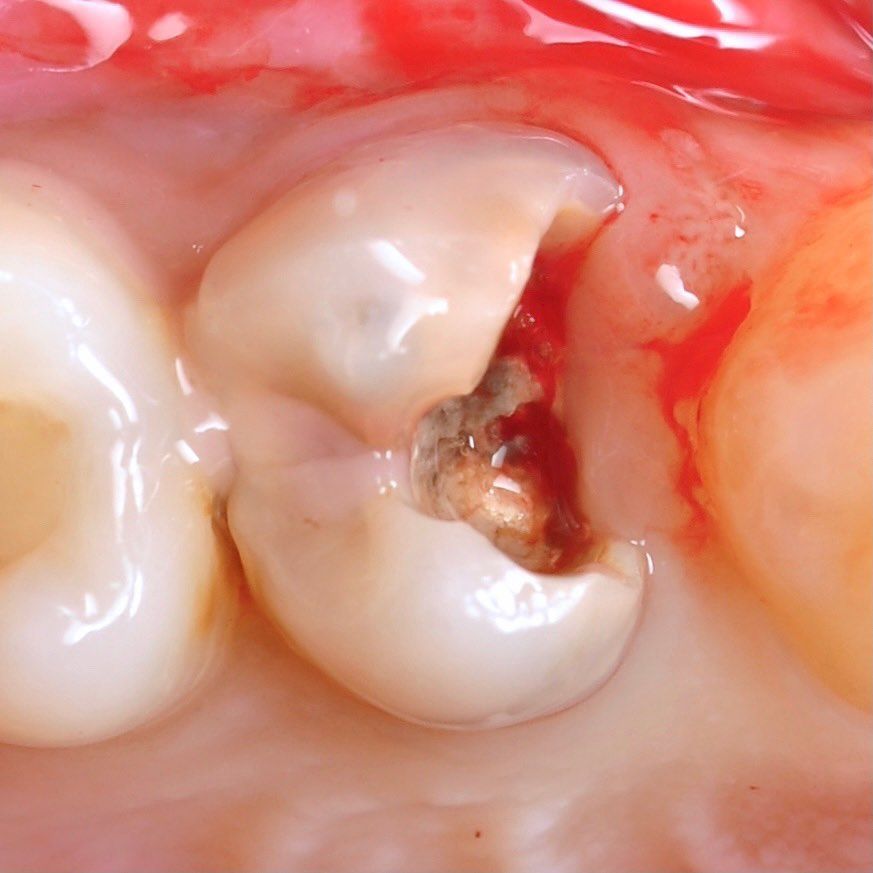

удаление кариеса

Оба заболевания носят воспалительный характер и являются следствием нелеченого кариеса. Воспаление внутри зуба – далеко не редкое явление, его опасность в том, что оно оказывает разрушительное действие на кость и окружающие ткани. Кариес мы можем увидеть, а вот воспаление может протекать незаметно и развиваться безболезненно.

Если вовремя не диагностировать проблему и не провести лечение, это может привести к потере зуба, что в дальнейшем потребует восстановления костной ткани для имплантации. Мы имеем большой опыт в лечении каналов и добиваемся отличных результатов с помощью качественной механической и медикаментозной обработки, которая позволяет полностью устранить воспаление.